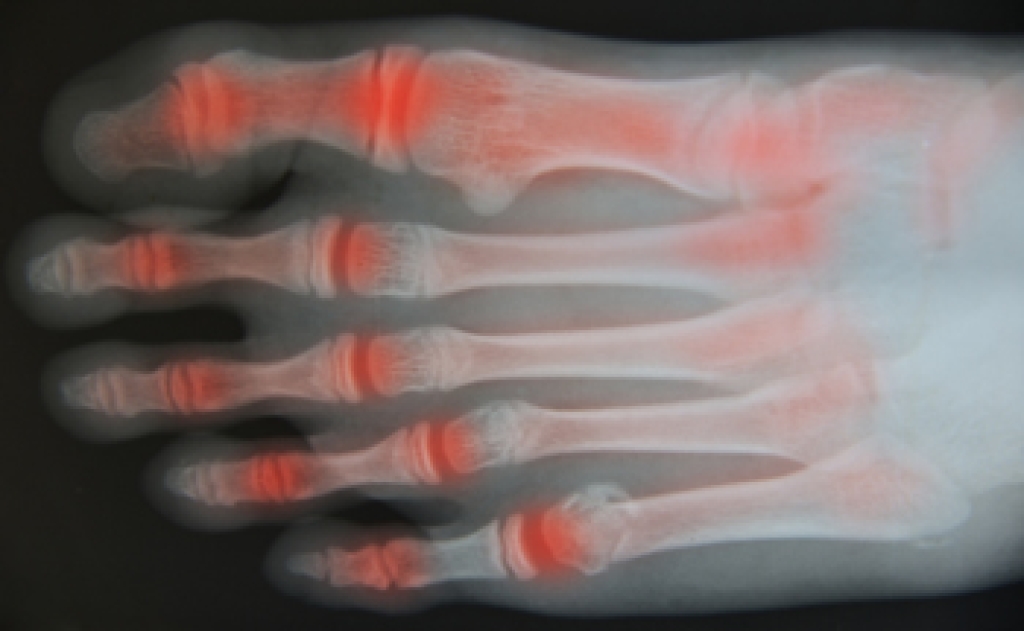

Osteoarthritis and Its Impact on Foot Health

Osteoarthritis is a degenerative joint condition that occurs when cartilage wears down over time, leading to pain and stiffness. In the feet, it often affects joints in the toes and midfoot, making walking uncomfortable. Causes include aging, excess body weight, genetic predisposition, and other forms of arthritis that contribute to joint damage. Symptoms include pain, swelling in foot joints, reduced flexibility, and discomfort that may worsen at night. Persistent foot pain can interfere with daily activities and overall quality of life. A podiatrist can diagnose the condition, recommend supportive footwear, provide custom orthotics, and develop a treatment plan to reduce pain and improve mobility. If you are experiencing ongoing foot discomfort or swelling, it is suggested that you consult a podiatrist who can offer effective relief and management solutions.

Arthritis is a term that is commonly used to describe joint pain.  The condition itself can occur to anyone of any age, race, or gender, and there are over 100 types of it.  Nevertheless, arthritis is more commonly found in women compared to men, and it is also more prevalent in those who are overweight. The causes of arthritis vary depending on which type of arthritis you have. Osteoarthritis for example, is often caused by injury, while rheumatoid arthritis is caused by a misdirected immune system.

Arthritic symptoms range in severity, and they may come and go. Some symptoms stay the same for several years but could potentially get worse with time. Severe cases of arthritis can prevent its sufferers from performing daily activities and make walking difficult.